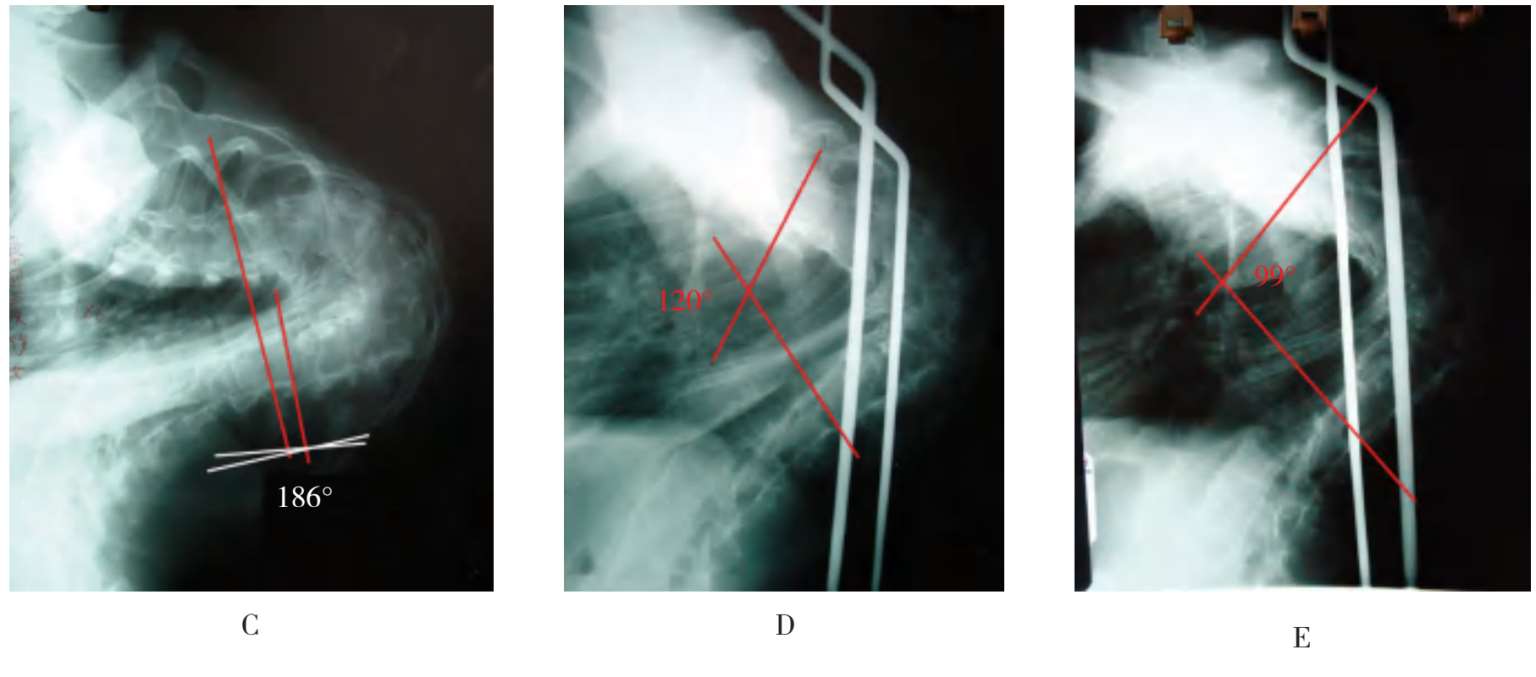

患者,女,17岁,先天性重度胸椎侧弯合并重度胸廓塌陷畸形(图3-9A、图3-9B),于2002年1月4日入院,术前X线片胸椎侧弯Cobb’s角186°(图3-9C),右侧胸廓严重塌陷,心肺功能受到严重影响,心跳加快,呼吸困难,口唇、甲床发绀。曾走遍全国各大医院,未得到收容治疗,特来我院要求手术。经颅盆牵引30天,胸椎侧弯从186°变成120°(图3-9D),继续牵引至45天胸椎侧弯变成99°(图3-9E)。然后行胸廓塌陷矫形术,术中将4条肋骨折弯变圆,吊在颅盆装置的立柱上,中间通过橡皮条做弹性牵引,3周后拆除牵引线,见胸廓已扩张变圆,外观明显改善(图3-9F至图3-9I),呼吸量增加,碳氧交换明显改善,以往的口唇、甲床发绀等缺氧现象恢复正常,给下一步脊柱侧弯矫正手术带来安全。于同年3月12日在颅盆牵引、局部浸润麻醉下,做了弹性分叉生长棒脊柱矫形术,术后恢复良好,身高增加22cm(图3-9J至图3-9M)。术后随访4年,一切均好,内固定尚未拆除。

A.后面观,左侧剃刀背明显,右侧胸廓严重塌陷。B.侧面观,脊柱后侧凸明显,右侧胸廓严重塌陷肋骨变直,肋前缘翘起,胸腔矢状径加大,躯干部缩短。C.胸椎后侧凸Cobb’s角186°,为脊柱侧弯患者中最大的角度。其弯曲段已形成U形襻,比180°还超过6°,为一例稀有病例。D.经颅盆牵引30天,胸椎侧凸从186°变成120°。E.继续牵引至45天胸椎侧凸变成99°。下一步先做胸廓成形术,后做脊柱侧凸弹性分叉生长棒矫形术,因为对重度脊柱弯曲只有颅盆牵引加弹性分叉生长棒的治疗方法,才能产生内支撑内固定的作用,其他内固定器械难以发挥作用。F.术前,脊柱侧凸合并重度胸廓塌陷畸形。G.经颅盆牵引后胸廓塌陷大部改善。H.将4条肋骨折弯变圆后,用粗丝线加橡皮条固定在颅盆装置的立柱上做水平牵引。I.胸廓成形术已完成,拆除牵引线后见胸廓塌陷已隆起变圆,胸腔容积加大,碳氧交换明显改善,口唇、甲床发绀消失。J.在颅盆牵引局部浸润麻醉下的卧位。K.弹性分叉生长棒的固定方法,1棒与2棒的安装,椎板下钢丝固定在1棒上,提肋钢丝固定在2棒上,两棒交替撑开,弹簧已被压缩,使两棒之间形成矩形面,使其产生生物力学稳定效应。L.内固定术后戴颅盆环早期下床活动,躯干部延长,身高增加22cm,人体重心居中,行走方便,人体外形大为改善。M.背面观

图3-9 典型病例介绍